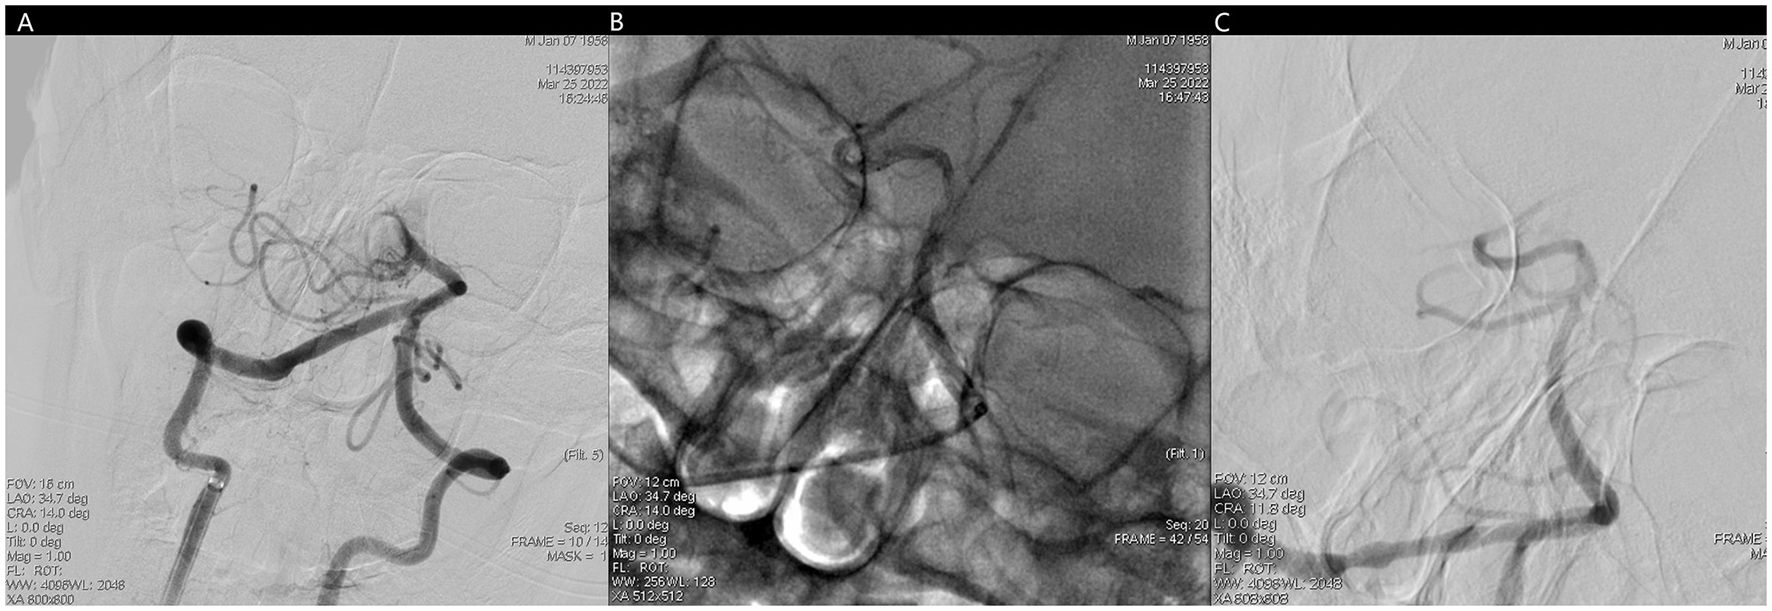

Figure 4

(A) No forward blood flow far from the middle of the basilar artery. (B) Fluoroscopic image of trevo stent after positioning and release. (C) Unobstructed basilar artery after mechanical thrombectomy.

Miraculously, we finished the surgery conversation and got the family member's signed consent for the surgery. 6F length sheath (Neuron Max, Punumbra, USA) was placed into vertebral artery. Diagnosic angiogram showed that the original occluded segment was unobstructed, but there was no forward blood flow far from the middle of the basilar artery, which was imaged normal supplied by left vertebral artery. A intermediate catheter (Catalyst 6, Stryker, USA) was advanced through the length sheath over a 0.014 inch microguidewire and 150 cm microcatheter, which was placed near the clot. Then thrombo-aspiration was performed. Diagnosic angiogram showed BA was recanalized and resulted in mTICI 3 flow.